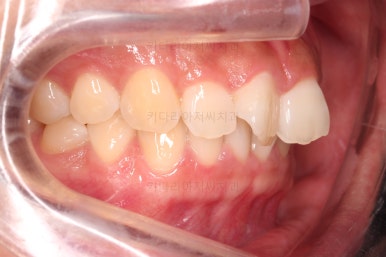

1. 초진

초진 시 입안의 모습입니다.

어금니 쪽은 약간 삐뚤긴 하지만 꼭 교정해야 할 정도는 아니고, 불편감 없이 비교적 잘 맞물리는 상태였습니다.

다만, 앞니ㅉㄱ이 공간이 부족해서 중간 치아들이 많이 회전되어있는데, 이를 환자분들의 표현에 따르면 "나비치아" 라고 부릅니다.

위아래 중간 앞니가 모두 나비치아처럼 되어있고요.

윗니가 아랫니보다 앞쪽으로 나와 있는 모습에 아래앞니가 윗니쪽으로 깊숙이 올라간 "과개교합" 양상을 보였습니다.